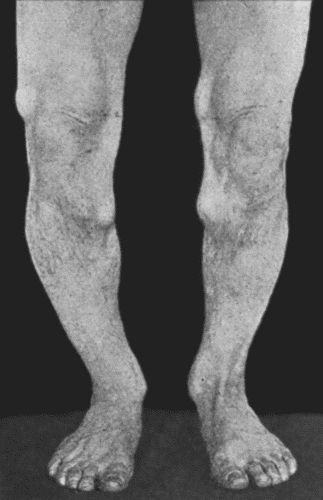

14.Leg Ulcers associated with Varicose Veins 71

67.Extensive Varix of Internal Saphena System on Left Leg 291